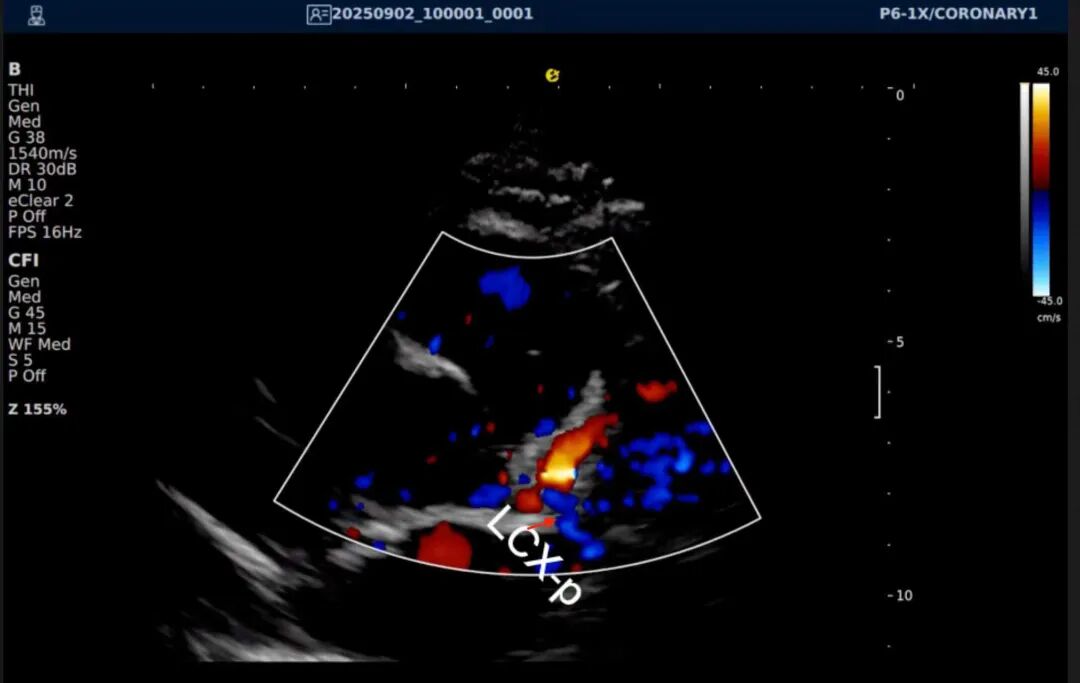

以下为逸超医疗(ESI)设备采集的冠脉图像,清晰展示了其在二维成像、彩色多普勒及频谱多普勒方面的表现:

左右滑动查看更多

心脏冠脉超声